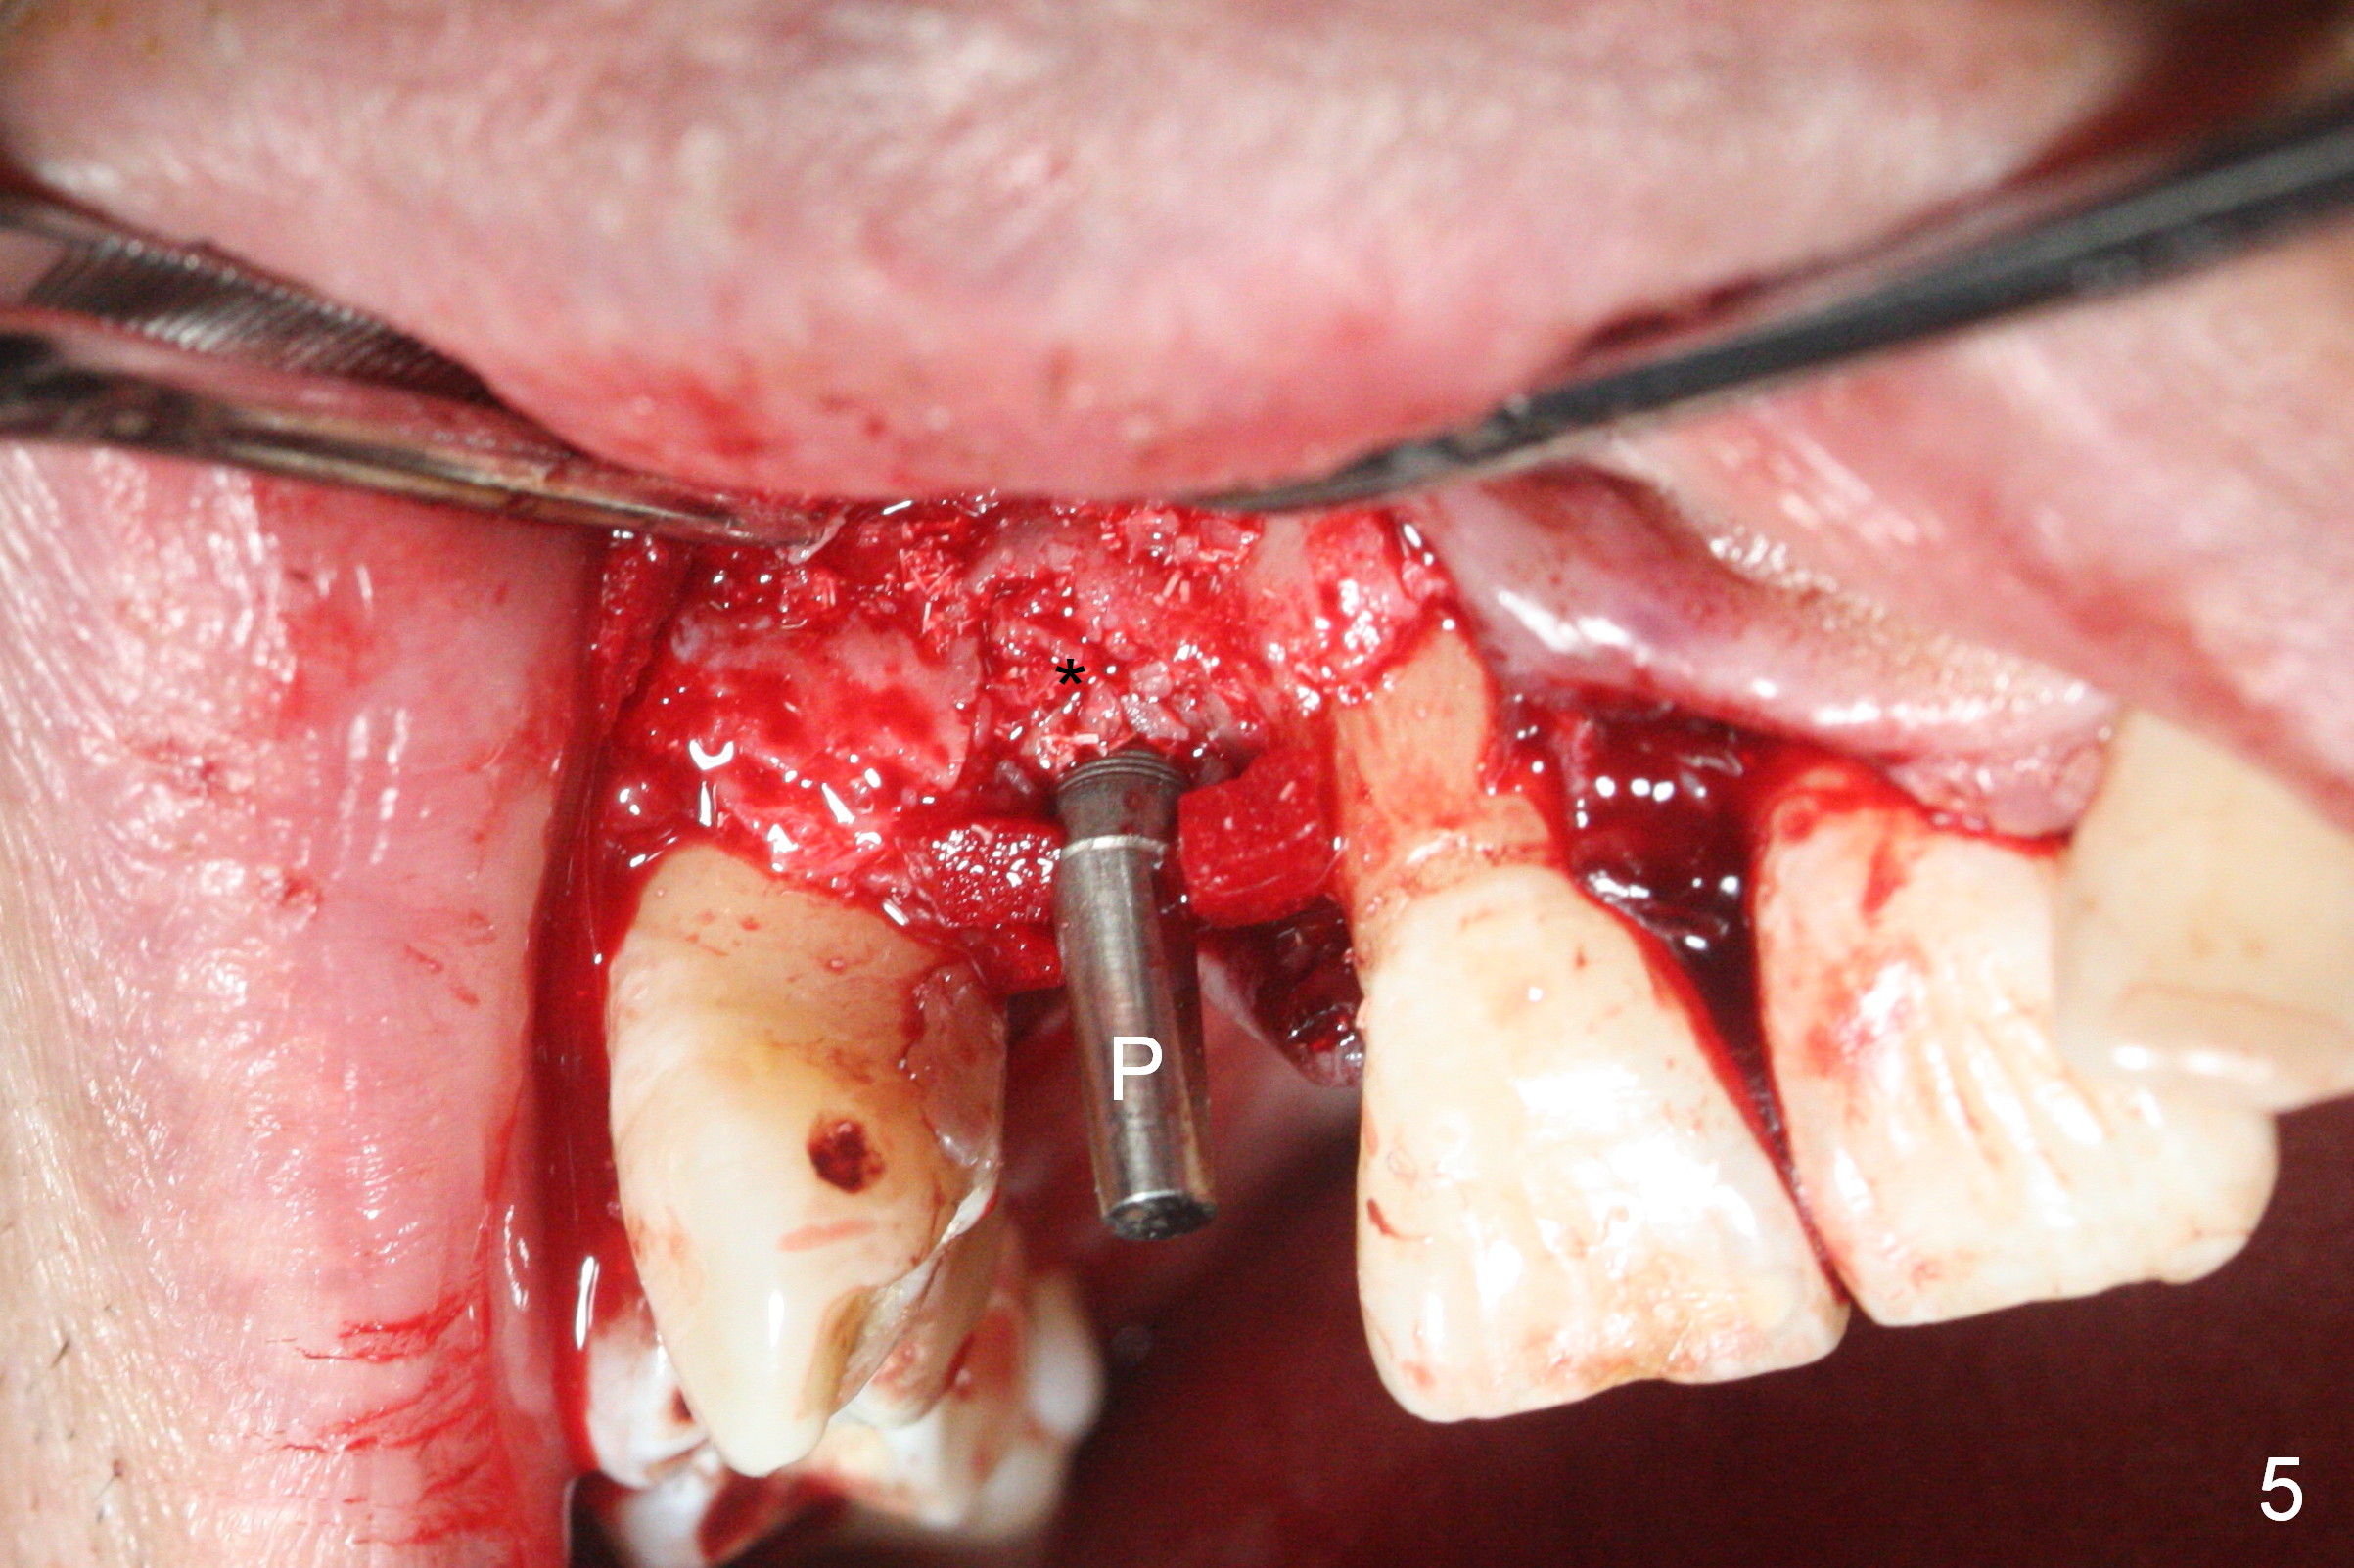

When the flaps are raised, the buccal plate is found to be perforated (Fig.2 *); osteotomy is being established in the narrow palatal wall (<). When a 3x17 mm (tissue-level) 15 ° 1-piece implant is placed (Fig.3,5 P), the incisal end of the implant is between the incisal edge of the central incisors and that of the tooth #10 (Fig.6) so that the temporary crown (Fig.7 T) is slightly buccal with sufficient palatal clearance with the opposing dentition.